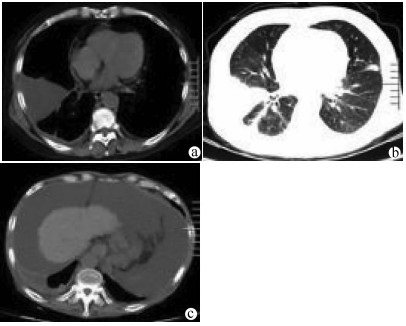

高原地区体外肝切除联合自体肝移植术治疗晚期肝泡型包虫病的术后并发症及其防治策略

田青山, 冯少培, 郭亚民, 韩秀敏, 赵顺云, 叶成杰, 安永德, 吴世乐, 王向前, 郑海波, 朱文君, 阿吉德, 高伟, 潘洪帅

2021, 37(9): 2153-2160. DOI: 10.3969/j.issn.1001-5256.2021.09.029

摘要(1294) HTML (489) PDF (3321KB)(54)

摘要:

目的  探讨高原地区体外肝切除联合自体肝移植术治疗终末期肝泡型包虫病的术后并发症并探讨防治策略。  方法  收集青海省人民医院2013年1月— 2019年3月接受自体肝移植术的11例终末期肝泡型包虫病患者的手术资料及随访资料,对术中及术后情况进行分析。  结果  11例患者均成功行自体肝移植术,无术中死亡,其中2例(18.18%)行半离体肝切除,9例(81.82%)行全离体肝切除。肝后下腔静脉重建方式中,采用自体大隐静脉进行重建者2例(18.18%),采用人造血管重建者4例(36.36%),5例(45.45%)保留自体肝后下腔静脉。胆道重建方式中,8例(72.73%)行胆肠吻合术,3例(27.27%)行胆管端端吻合术。11例患者的术后并发症主要有出血2例(18.18%);胆汁漏、腹腔感染4例(36.36%),胆肠吻合口狭窄1例(9.09%), 血栓2例(18.18%),肺部感染、胸腔积液2例(18.18%);包虫复发1例(9.09%)。11例患者发生围术期死亡2例(18.18%),其余9例(81.82%)患者均好转出院。  结论  出血、胆道并发症和感染是造成高原地区自体肝移植患者死亡的主要原因,精准把握手术适应证、术前仔细多学科评估、术中精湛的操作、外科技术流程的标准化及精细的围术期管理是降低自体肝移植术围术期病死率、避免和减少术后并发症以及使患者获得长期良好生存的关键。